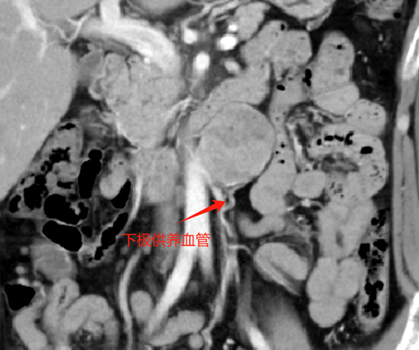

7、 我们采取了“先游离外下侧,掀起肿瘤向内上侧推进”的策略小心游离肿瘤。在肿瘤下极发现供瘤血管,无明显搏动,考虑为静脉,hem-o-lok夹闭后切断。

本例诊断为副神经节瘤,其与肾上腺内嗜铬细胞瘤同来源于神经节组织,位于交感神经旁,腹膜后主动脉和下腔静脉旁较多见。副神经节瘤为功能性神经内分泌肿瘤,好发于30~50岁,占腹膜后肿瘤的1%~3%,多位于肾动脉至腹主动脉分叉水平的主动脉旁区域。副神经节瘤为富血供肿瘤,增强后明显强化,动脉期显著,可有多支血管同时供应,肿块周围或实性成分内可见迂曲增粗的肿瘤血管,提示完整切除肿瘤、同时避免出血为手术团队提出了很大挑战。